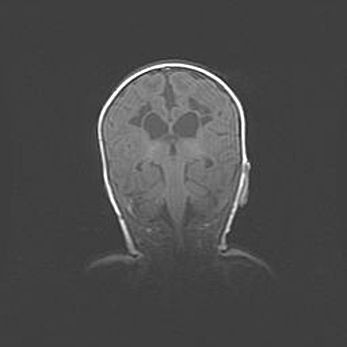

Аномалия Денди-Уокера. Признаки гипоплазии мозолистого тела.

Возраст: 5 месяцев 3 дня

Вес: 5550 г

Пол: мужской

Окружность головы: 39 см

Срок гестации: 40 недель

Аномалия Денди-Уокера – это порок развития головного мозга, для которого характерна триада симптомов: гипотрофия или аплазия червя мозжечка и/или полушарий мозжечка, расширение четвёртого желудочка с формированием ликворной кисты задней черепной ямки, гипертензионная гидроцефалия различной степени.

Гипоплазия мозолистого тела относится к дефектам внутриутробного этапа развития мозговой ткани, возникающим в процессе закладки структур головного мозга, что происходит на начальных этапах развития эмбриона.